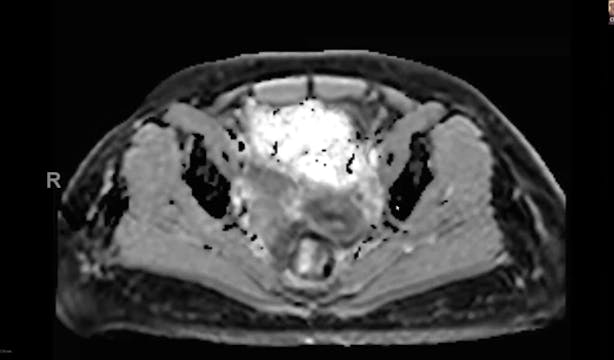

02/08/2023 - Dr. Christine Fisher - Radiation Oncology - US GYN

endometrial adenocarcinoma, para-aortic nodes, PET CT, diabetes, charcot arthropathy, groin nodes, pelvis, negative cervical margins, cisplatin, small bowel, Harkenrider, contouring, MRI, tumor, vaginal bleeding, relapse, persistence, cylinder, dose distribution, dosimetry, brachytherapy, fractionation, concurrent chemotherapy, parametrial area